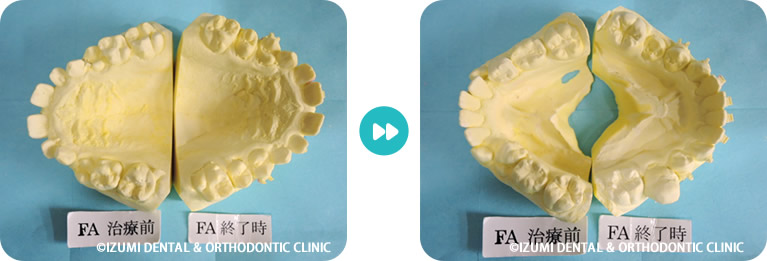

大人の矯正治療は出来るだけ見えにくい小さな矯正装置を利用して上の歯並びから歯ならび治していきます。埋伏している犬歯も萌出させていきます。

上顎の歯列がある程度改善してから下顎の歯列を見えにくいブラケットという矯正装置で整えていきます。埋伏している犬歯もだんだん萌出してきました。

MEAW(マルチループ)により咬合高径(咬み合わせの高さ)を改善して美しい咬み合わせに治療していきます。(矯正開始から3カ月後)

終了時2か月前(1年3ヶ月後)